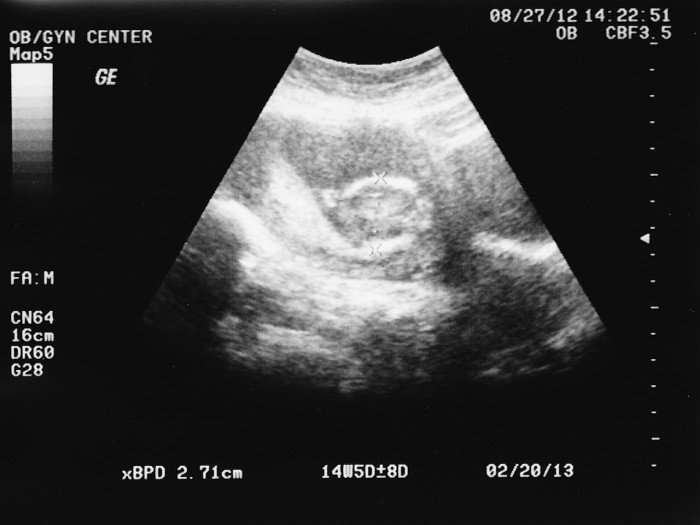

2012-08-27-Ultrasound-04-web Post author By sean Post date October 13, 2012 No Comments on 2012-08-27-Ultrasound-04-web Leave a Reply Cancel replyYour email address will not be published. Required fields are marked *Comment * Name * Email * Website